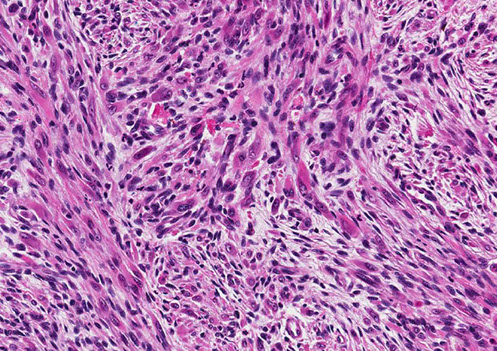

Kaposiform Hemangioendothelioma

- also Acquired Tufted Angioma

Rare, locally aggressive neoplasm of infants / kiddos in skin retroperitoneum and bone

- death from extensive dz and severe coagulopathy (Kasabach-Merritt syndrome)

- no mets

Micro: infiltrating nodules (cannon-balls) and sheets of compact spindle cells c slit-like lumina

- platelets get stuck in whorled nodular vascular channels

- has dilated lymphatic channels at periphery

IHC: (+) VEGFR-3

- GLUT-1 negative (unlike infantile hemangioma)

DDx: Acquired tufted angioma (looks identical microscopically, BUT just a small skin lesion in adults and is not assoc c KM syndrome)

Tx: may be a difficult decision to remove tumor bc of low platelets in pts

Px: 10% mortality; usually when assoc c bleeding from low platelets in KM syndrome